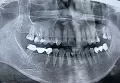

Отпал кусочек зуба (верхняя шестерка), болезненных ощущений не было. После осмотра врач констатировал острый кариес, мне удалили нерв, почистили канал, положили лекарство и поставили временную пломбу на неделю. Через 40 минут после данной процедуры при наклоне из левой ноздри полилась жидкость грязно-розового цвета и резкого неприятного запаха (типа хлорки или какого-либо лекарства). Второй день периодически жидкость выходит из носа.

Сегодня была на приеме, сделали снимок, сказали ничего страшного - просто лекарство попало в гайморовые пазухи. Прописали антибиотики. Зуб не беспокоит, но кусать на него очень больно. У меня маленький ребёнок на ГВ, приём антибиотиков подразумевает прекращение кормления, но это очень серьёзная проблема для меня.